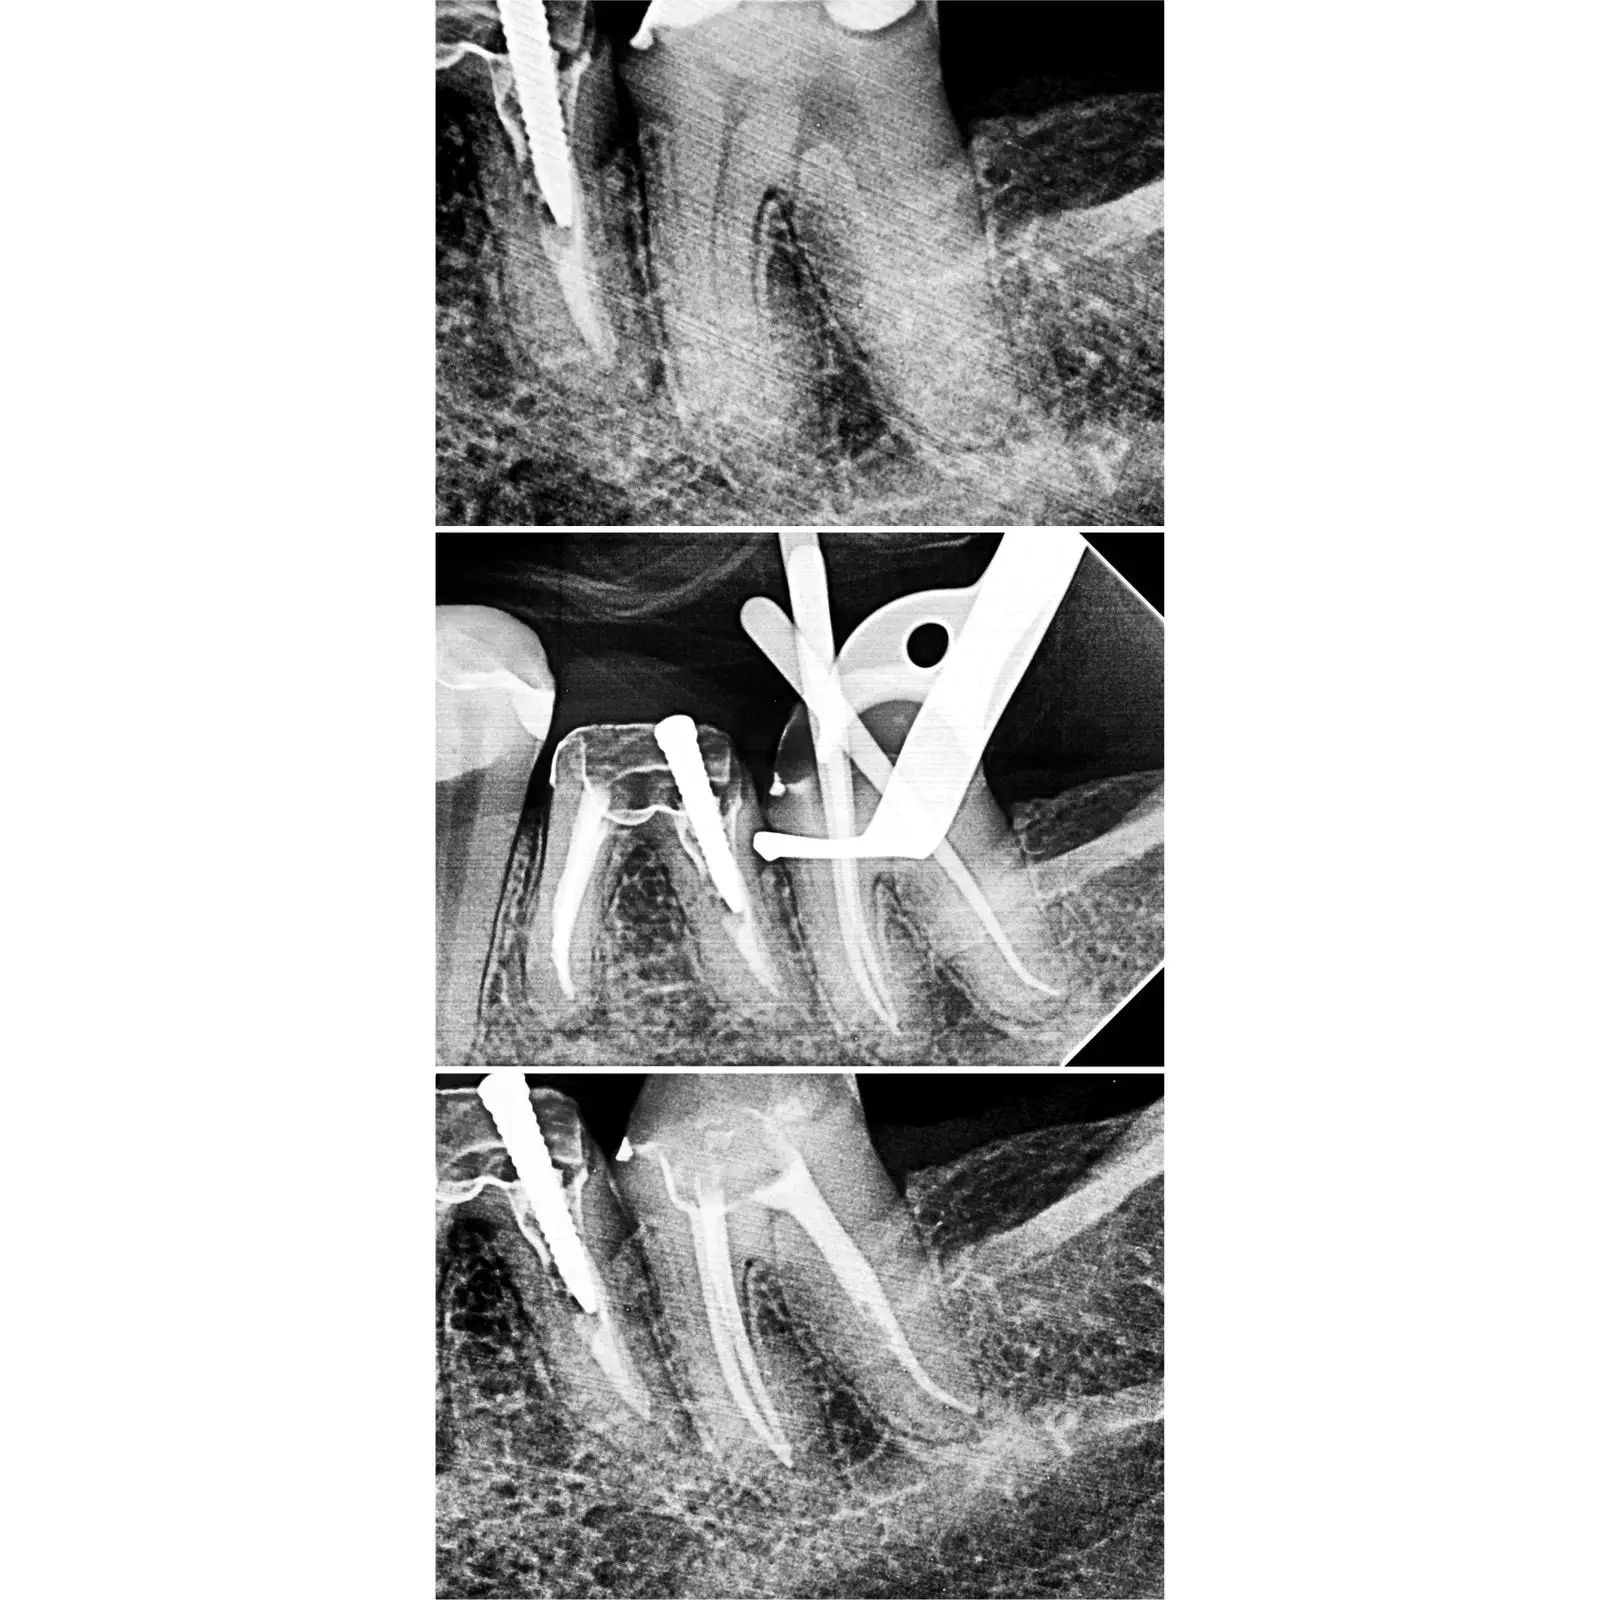

Portfólio

Casos Clínicos

Resultados que demonstram precisão técnica e excelência.